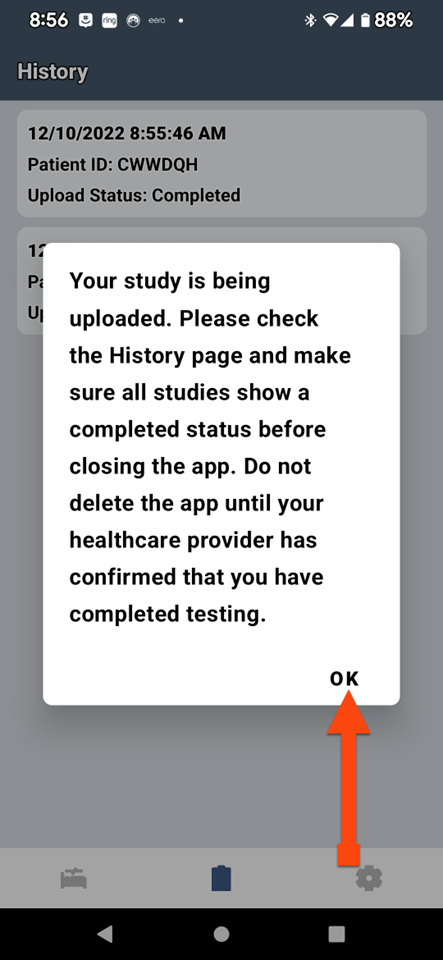

SLEEPIMAGE APP (Android)

SLEEPIMAGE APP (Android)

SLEEPIMAGE APP (Android)

SLEEPIMAGE APP (Android)

SLEEPIMAGE APP (Android)

SLEEPIMAGE APP (Android)

SLEEPIMAGE APP (Android)

SLEEPIMAGE APP (Android)

SLEEPIMAGE APP (Android)

SLEEPIMAGE APP (Android)

SLEEPIMAGE APP (Android)

SLEEPIMAGE APP (Android)

SLEEPIMAGE APP (Android)

SLEEPIMAGE APP (Android)

SLEEPIMAGE APP (Android)

SLEEPIMAGE APP (Android)

SLEEPIMAGE APP (Android)

SLEEPIMAGE APP (Android)

SLEEPIMAGE APP (iPhone)

SLEEPIMAGE APP (Android)

SLEEPIMAGE APP (Android)

SLEEPIMAGE APP (Android)

SLEEPIMAGE APP (Android)

SLEEPIMAGE APP (Android)

SLEEPIMAGE APP (Android)

SLEEPIMAGE APP (Android)

SLEEPIMAGE APP (Android)